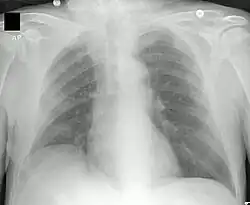

Neumonía apical derecha: en la FQ, la infección crónica da lugar a la destrucción del parénquima pulmonar, ocasionando por último la muerte por insuficiencia respiratoria. | ||